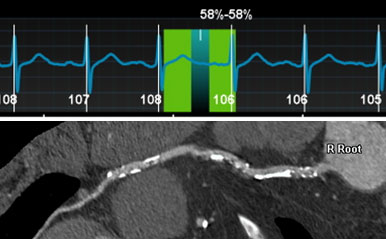

次に、当院における最適な心位相検索についての検討では上記で述べた機能とSmart Phase機能により、約90%の症例が冠動脈の動きが最も少ない最適な心位相で自動再構成された。これにより、撮影後の心位相検索にかかる時間と手間の大幅な短縮となった。

被ばく線量については、Auto Gating機能によって最適な照射心位相が自動で決定されることにより、大幅に低減していた。また、不整脈症例に対しても、不整脈回避機能と上記までの機能の組み合わせにより、モーションアーチファクトのない画像が得られている。

RevolutionApexElite_Sakai02.jpg

図1) 高心拍症例の右冠動脈CPR